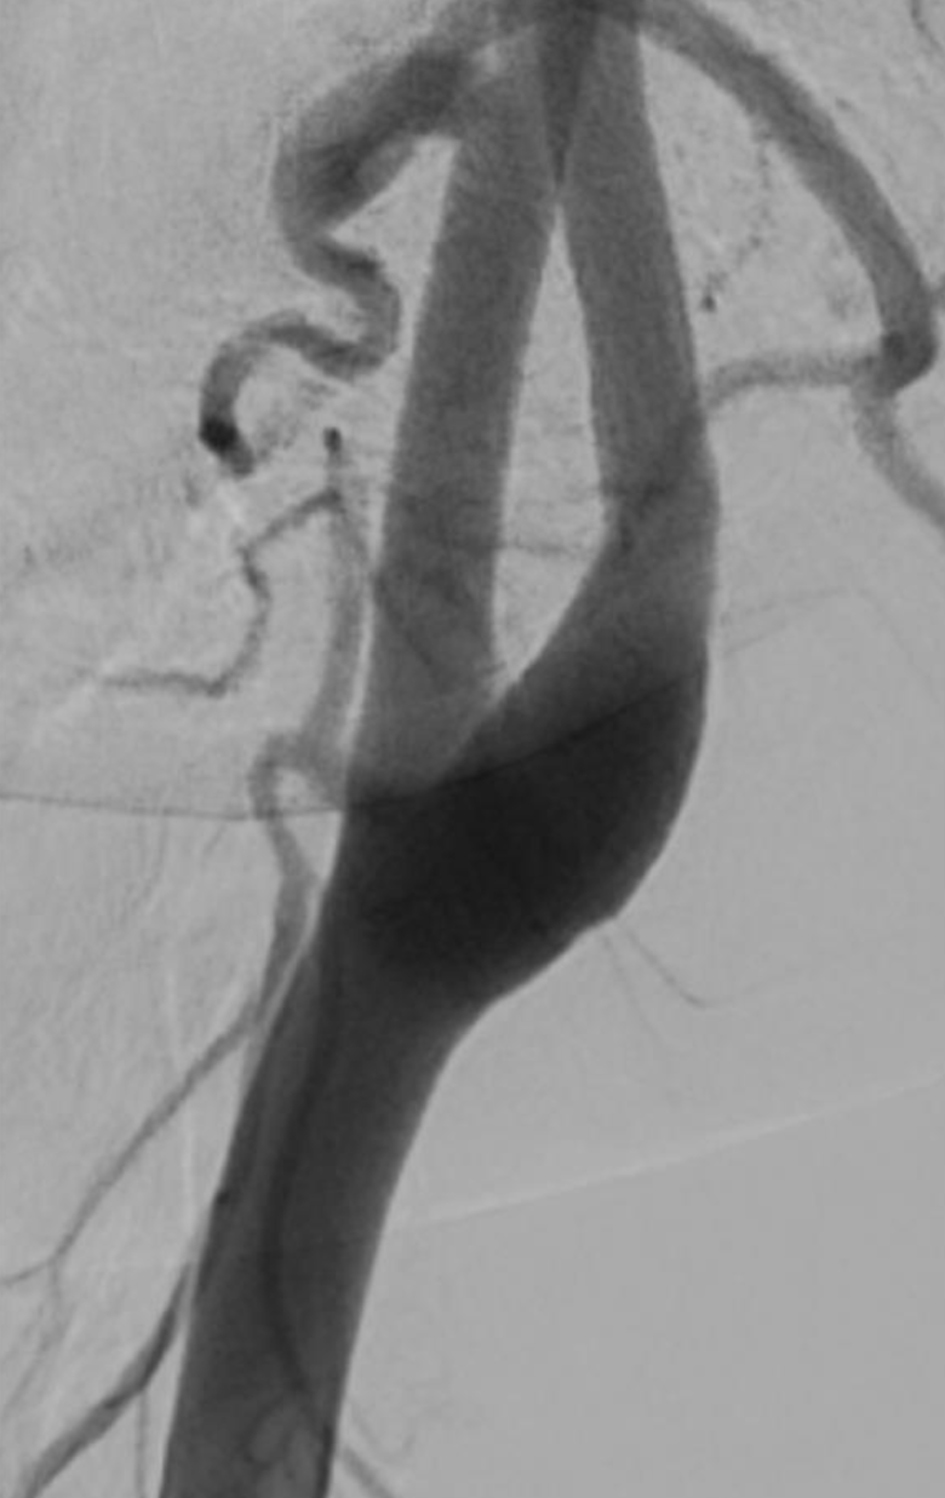

The following day, no apparent hemorrhagic extension was observed. On carotid artery ultrasonography, there was a mobile lesion at the origin of the left ICA (Fig. 2). Further examination with three-dimensional computed tomography angiography (3D-CTA) revealed the presence of irregular contrast in the posterolateral wall of the left cervical ICA origin (Fig. 3a-d). MRI plaque image revealed a structure that was T1 isointense (Fig. 4a) and T2 high intense (Fig. 4b) with the vessel wall, protruding into the lumen (Fig. 4). On the second day, cerebral angiography revealed a shelf-like structure on the posterior wall of the left ICA origin (Fig. 5a), and the left MCA was recanalized. Cerebral angiography revealed pooling of blood flow on the rostral side of the lesion (Fig. 5b).

Figure 5. (a) Cerebral angiography revealed a shelf-like structure on the posterior wall of the left internal carotid artery origin on the second day. (b) Cerebral angiography revealed pooling of blood flow on the rostral side of the lesion.

Treatment

Figure 7. Cerebral angiography performed 87 days after symptom onset showed that the shelf-like structure on the posterior wall of the origin of the left internal carotid artery had disappeared.

CW is a subtype of fibromuscular dysplasia wherein the pathological tissue shows few changes in the media and is mainly characterized by fibrous hyperplasia of the intima [4, 8]. The diagnosis of CW is often based on morphology as seen on radiographic imaging. Cerebral angiography and CTA are useful diagnostic tools [9], typically revealing a contrast defect caused by a shelf-like structure on the posterior wall of the origin of the ICA, with blood flow pooling on the rostral side of the structure [7, 10]. This pooling of the blood promotes thrombus formation, which can result in cerebral infarction [1]. In the present case, CTA revealed a shelf-like structure on the posterolateral wall of the origin of the ICA, and this was also seen on cerebral angiography, alongside blood flow pooling on the rostral side of the structure. These imaging findings are strongly suggestive of CW.